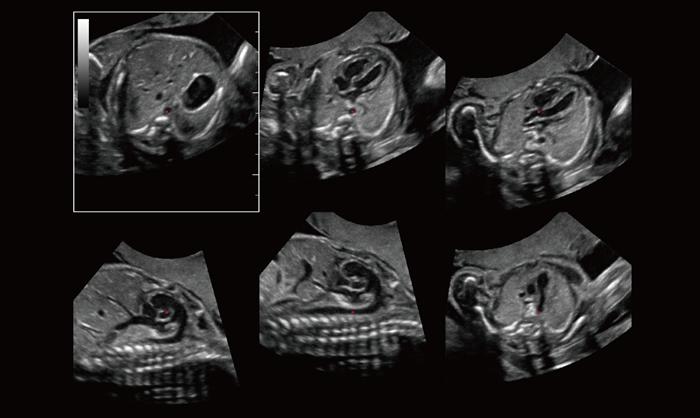

Care este diferenta dintre ecografia 2D, 3D si 4D?

Foto 1/7